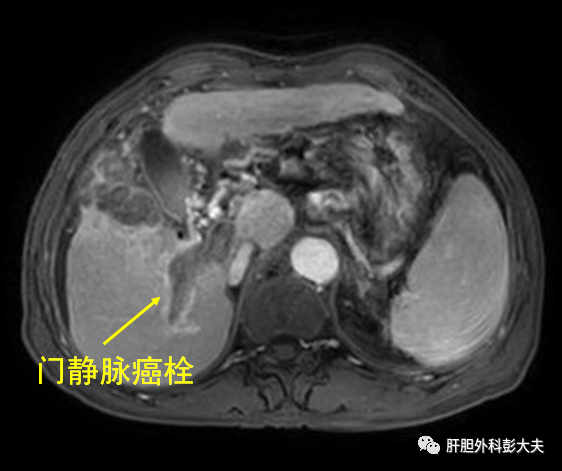

黑龙江的周先生5个月前因右上腹部胀痛不适,行腹部B超检查,发现肝内有多个肿瘤,同时还伴有门静脉主干及分支癌栓形成,当地医院考虑是晚期肝癌,建议到上级医院治疗。于是,周先生来到北京世纪坛医院,找到了肝胆肿瘤外科。科主任彭吉润教授和同事详细询问了患者病史,仔细阅读了患者的影像学等辅助检查资料,考虑患者诊断很明确,但是由于肿瘤多发,并且合并大血管如门静脉以及肝静脉内的癌栓,肿瘤还转移到了左侧肾上腺,因此不能做根治性手术切除了(图1)。

图1. 右肝巨块型肝癌伴门静脉和肝静脉癌栓